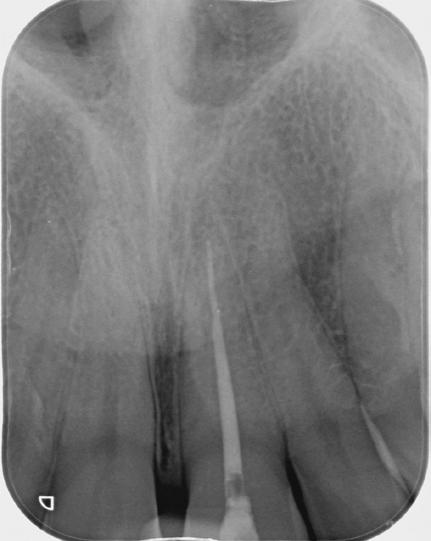

Radiographic Findings

Preoperative periapical radiographs revealed a severely calcified root canal system. The canal outline was barely visible, indicating significant narrowing of the canal space.

This case demonstrates that successful endodontic treatment of teeth with severely calcified canals is possible without the routine use of CBCT or guided access. Careful interpretation of periapical

Pre-op xray showing severely calcified root canal of tooth 21